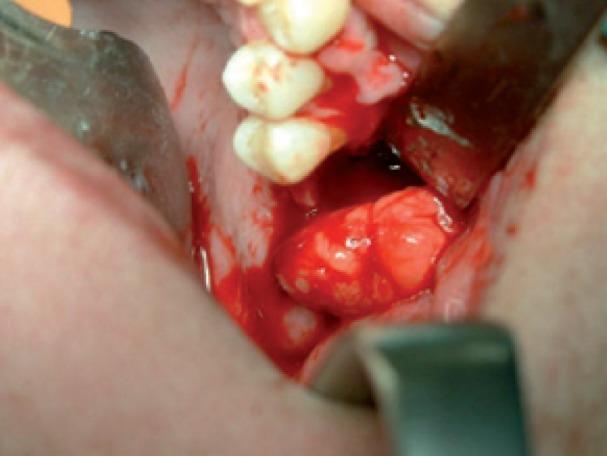

The use of pedicled buccal fat pad flap (BFP) has proved of value for the closure of oroantral and oronasal communications and is a well-established tool in oral and maxillofacial surgery. Otherwise, the perceived limitations of surgical therapy for bisphosphonate-related osteonecrosis of the jaws (BRONJ) have been widely discussed, and recommendations have largely been made to offer aggressive surgery only to stage 3 patients refractary to conservative management. Oroantral communication may be a common complication after sequestrectomy and bone debridement in upper maxillary BRONJ. We report a case series of stage 3 recalcitrant maxillary BRONJ surgically treated with extensive sequestrectomy and first reconstruction using pedicled BFP. All the cases presented an uneventful postoperative healing was uneventful without dehiscence, infection, necrosis or oroantral communication. We postulate that managing initially the site with BFP and primary closure may ensure a sufficient blood supply and adequate protection for an effective bone-healing response to occur. This technique may represent a mechanic protection and an abundant source of adipose-derived adult stem cells after debridement in upper maxillary BRONJ. We evaluate in this work results, advantages and indications of this technique.

带蒂颊脂垫瓣(BFP)的应用已被证明对关闭口鼻瘘和口鼻腔相通具有重要价值,是口腔颌面外科中一种成熟的工具。否则,人们普遍讨论了针对双膦酸盐相关性颌骨坏死(BRONJ)的手术治疗的局限性,并建议仅对第三期患者(对保守治疗有抗性的患者)进行积极的手术治疗。上颌骨 BRONJ 经病灶切除术和骨清创术后,可能会发生口鼻瘘。我们报告了一系列采用广泛病灶切除术和带蒂 BFP 首次重建治疗的第三期难治性上颌骨 BRONJ 病例。所有病例均无术后并发症,无愈合不良、感染、坏死或口鼻瘘。我们推测,最初用 BFP 处理该部位并进行一期闭合,可以确保足够的血液供应,并为有效的骨愈合反应提供充分的保护。在这种技术可能在上颌骨 BRONJ 清创术后提供机械保护和脂肪来源的成年干细胞的丰富来源。我们在这项工作中评估了该技术的结果、优点和适应证。